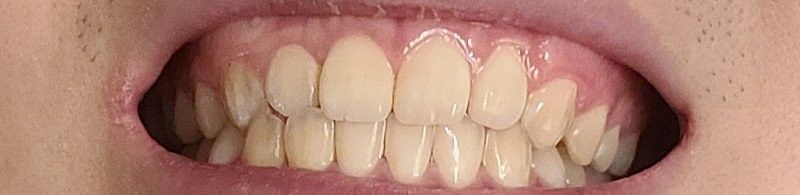

식사를 하거나 일상생활에서 교합을 하는데 큰 문제가 없다면 정상교합으로 판단합니다.

피개량이 적긴하지만 위에 치아가 아래 치아를 덮고 있다면 반대교합이나 절단교합이 아닌 정상교합의 범주에 있다고 판단을 하게 됩니다.